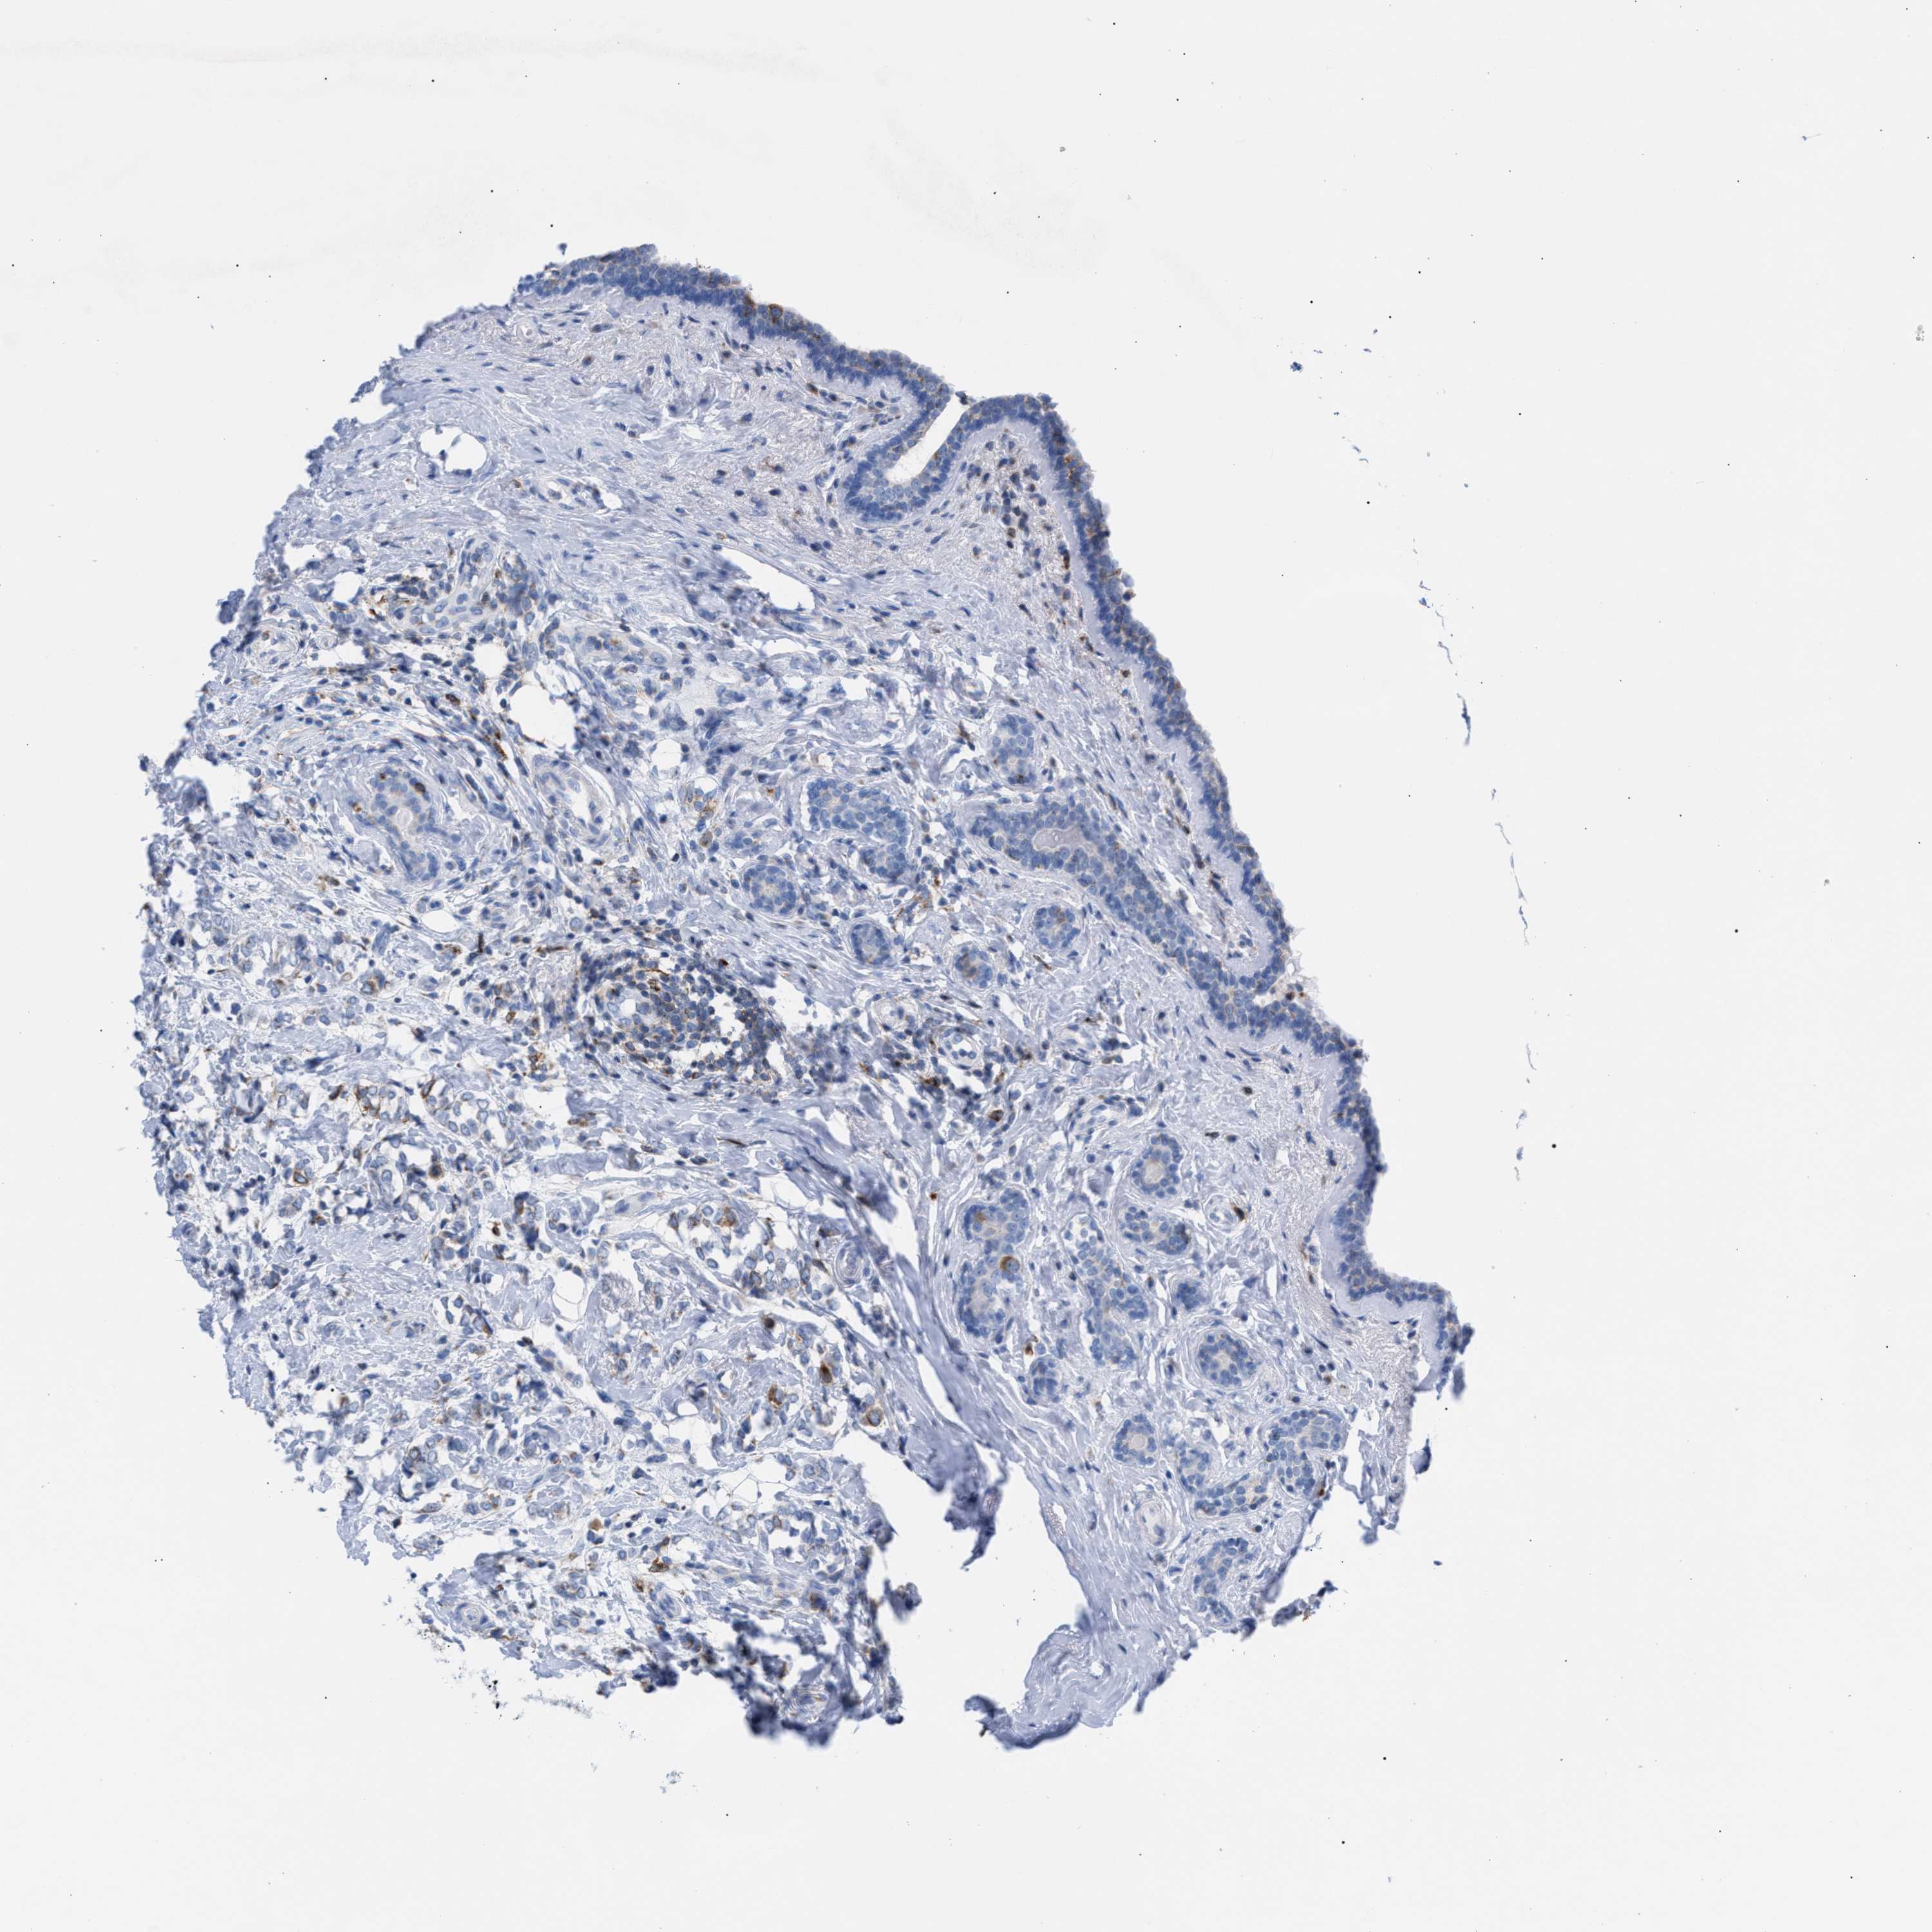

CANCER BREAST CANCER Show tissue menu

BRCA TCGA BRCA VALIDATION PROTEIN EXPRESSION